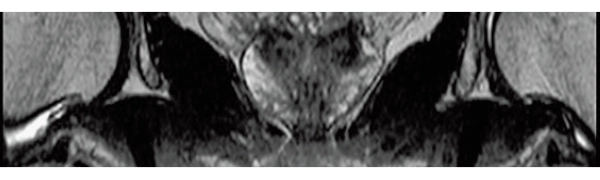

T2*WI Multi Echo,

0.38×0.38×2.0mm

0.35×0.40×3.0mm, 2:55